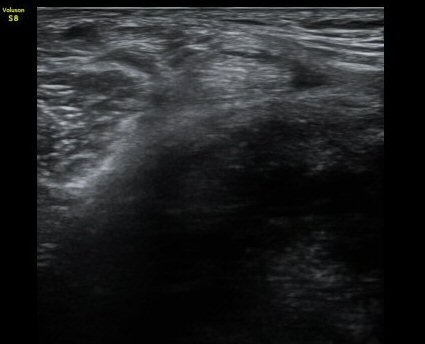

¹«¸­ µÚ ³»Ãø ¹Ý¸·¾çÈûÁÙ(semimembranosusu) Á¾´Ü¸é°Ë»ç¿¡¼­  ÈûÁÙÀÇ ºñÈÄ, ÈûÁ٠ǥÃþÀÇ ¼ö¾×

Àú·ù¿Í ÈûÁÙ ºÎÂøºÎ °æ°ñÀÇ ºÒ±ÔÄ¢ º¯È­°¡ °üÂûµÊ(±×¸² 3).